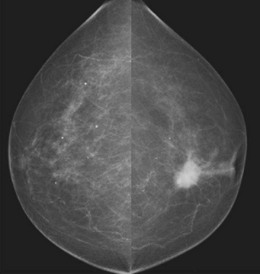

Accurate diagnosis of breast lesions depends on clinical assessment, backed up by mammography and/or breast ultrasound and pathological diagnosis, either by fine-needle aspiration cytology or core biopsy (‘triple assessment’) (Box 10.5 and Figs 10.15 and 10.16). Up to 5% of malignant lesions require excision biopsy for the diagnosis to be made. Magnetic resonance imaging is useful to investigate possible implant rupture, extent of cancer in a mammographically dense breast and as a screening tool in those with genetic markers – BRCA1 or 2. In the UK there are specific guidelines for the appropriate referral of patients with breast symptoms to specialist units where this assessment is carried out.